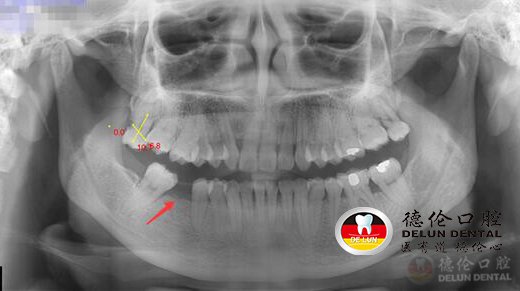

舒女士术前X光照片,下颌缺牙一颗

小蛀牙不及时处理,往后补牙也救不了你的牙齿!今天的种牙手术直播主角舒女士以“牙齿的教训”印证这一说法。谁能想到,舒女士右下颌缺失的那颗牙齿,开始只是一颗蛀牙?

浅龋基本没有感觉或只有轻微的酸痛,加之舒女士没定期到口腔机构检查牙齿。慢慢的,浅龋发展为中龋、深龋,舒女士想着吃点止痛药忍忍就过去了,仍未到医院就诊。之后蛀牙进展到了末期,牙齿结构缺损很大,只留下残根,牙齿只能面对被拔除的命运。